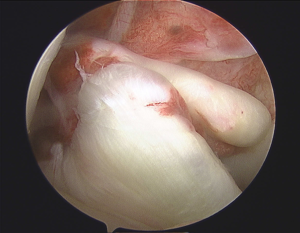

Reconstruction involves placing a graft inside the knee by arthroscopic surgery (keyhole). A

>90% success rate is normal with some deterioration over time depending upon other damage within the joint.

In the surgery a graft will be harvested to use to reconstruct the torn ligament. Usually two of the hamstring tendons are taken, but sometimes other suitable graft choices are used. This will be discussed with you prior to the operation. The remnants of the torn ACL are removed with keyhole surgery and tunnels are made in the tibia (shin bone) and femur (thigh bone) to allow the graft to be positioned across the knee. The new reconstructed ligament is then fixed at both ends to secure it in place.